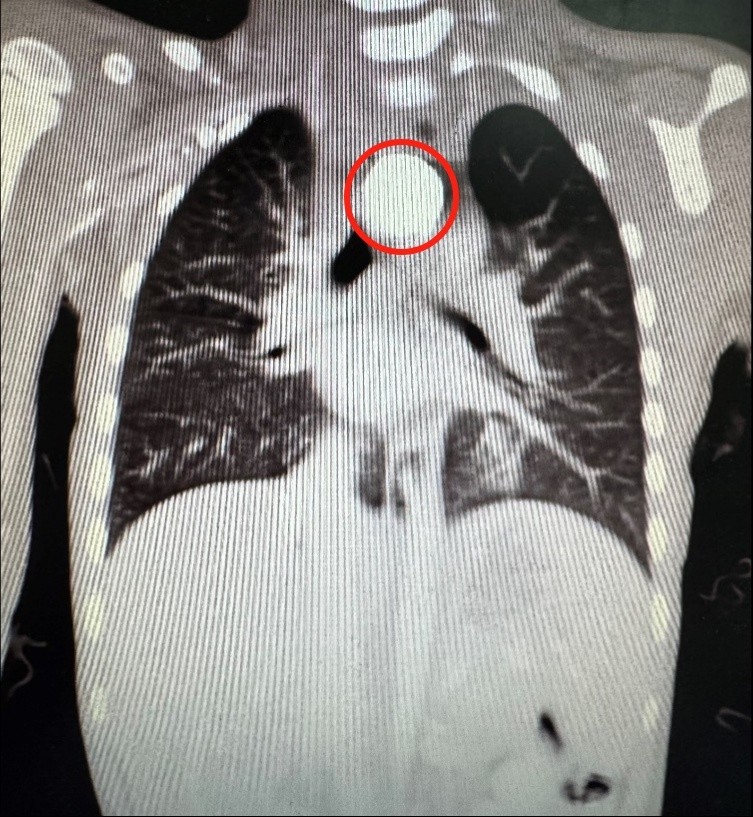

4岁的小雨(化名)因好奇吞了一枚纽扣电池,家人并未发现。第三天,小雨突发呕吐及发热,被送到当地医院。影像检查发现电池卡在食管胸上段,紧邻气管和主动脉。家人这才想起,其实小雨从三天前就已经开始一直不明原因哭闹了,推测误吞纽扣电池应该发生在三天以前。

为了防止纽扣电池移位造成更大范围损伤以及哭闹加剧中毒风险,当地医院经口气管插管下尝试胃镜下取异物,但食管腔内异物周围已形成溃疡,难以取出。由于风险高,小雨被转诊到珠江医院儿童重症医学科(PICU)。医院立即启动多学科联合救治机制,胸外科、小儿外科、消化内科、麻醉科等专家迅速会诊。